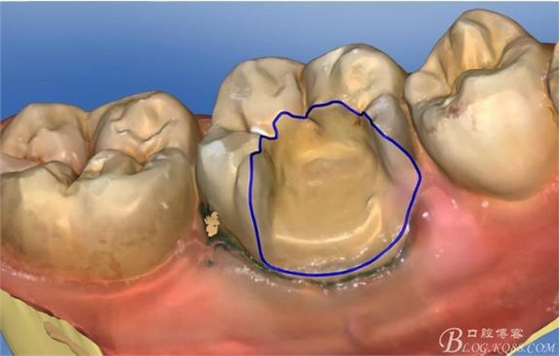

畫線是最關(guān)鍵的,線畫不好制出的修復(fù)體會出現(xiàn)邊緣缺損 或多 或少,醫(yī)生和技術(shù)配合

掃描 畫線 準(zhǔn)備研磨